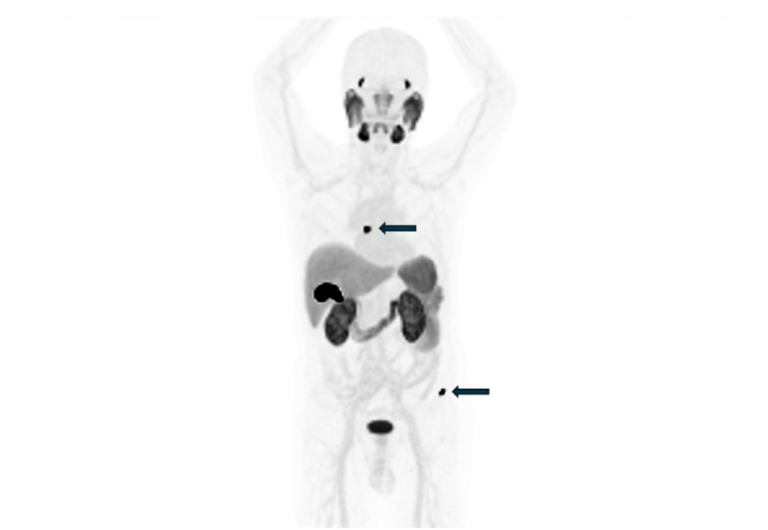

普瑞默生技放射新藥納首位病患 開啟大腸直腸癌精準診療新里程

普瑞默生技今(6)日宣布,其自主研發的放射標靶血管新生診療藥物新藥PB012重大進展,已於高雄某醫學中心完成第…